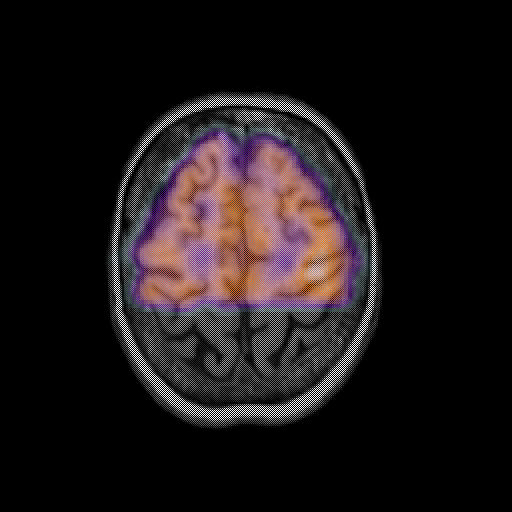

overlay: Slice 42

Slice 42

MRCBFCBF with

[Whole Brain Atlas Home Page] [Brain structure list] [Navigator Help Page]

Keith A. Johnson (keith@bwh.harvard.edu), J. Alex Becker (jabecker@mit.edu)